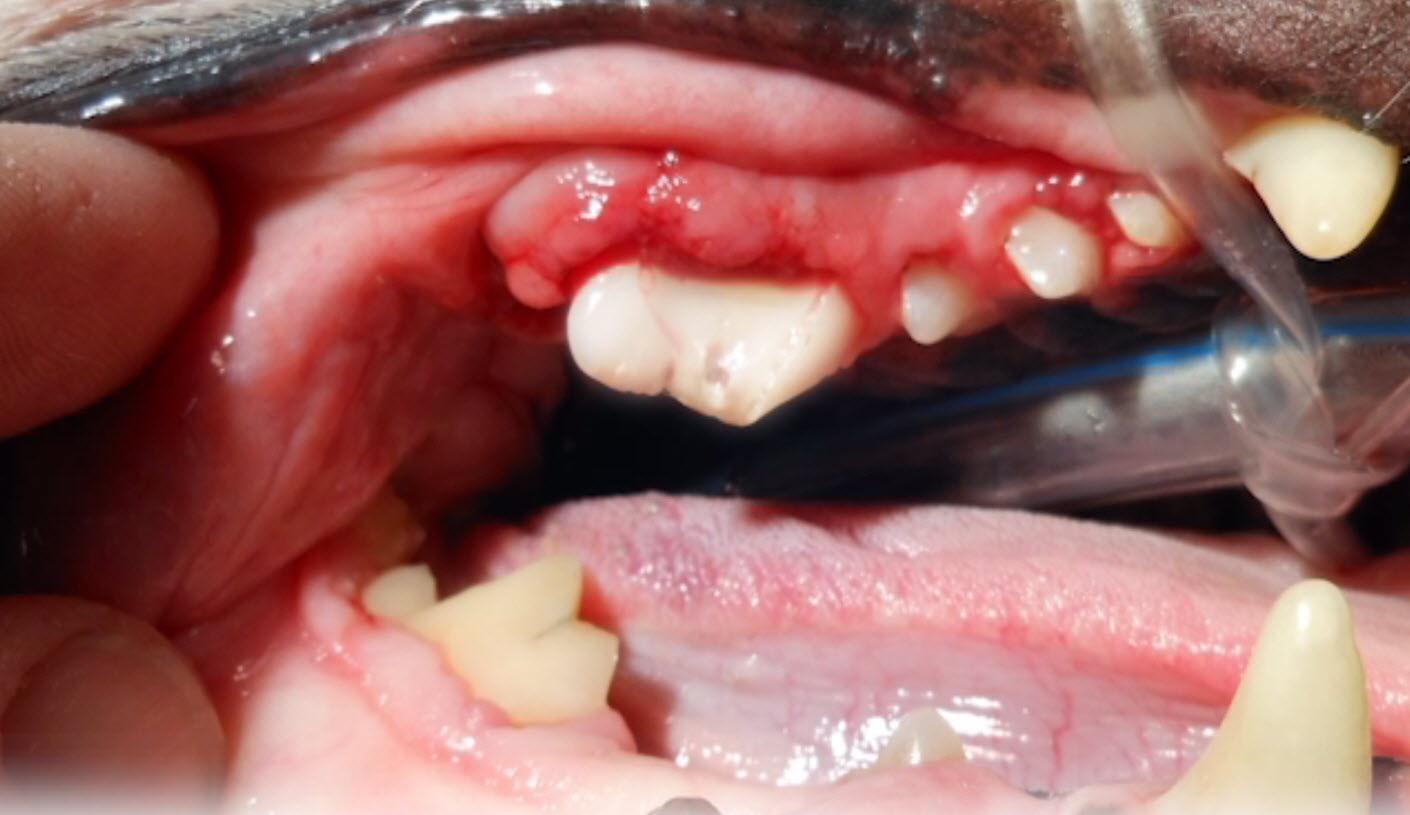

- Si podemos ver la cavidad bucal, estará enrojecida, inflamada o, en los casos más graves, ulcerada

- Al tocar podría producirse sangrado

- Gingivoestomatitis linfoplasmocitaria en perros (LPGS): parece que son casos con base inmunológica, poco frecuentes en perros y quizás relacionados con algunas razas. El tratamiento es complejo y el pronóstico reservado. [1]

Quisiera saber que son esas masitas en la parte de la geta de mi perra